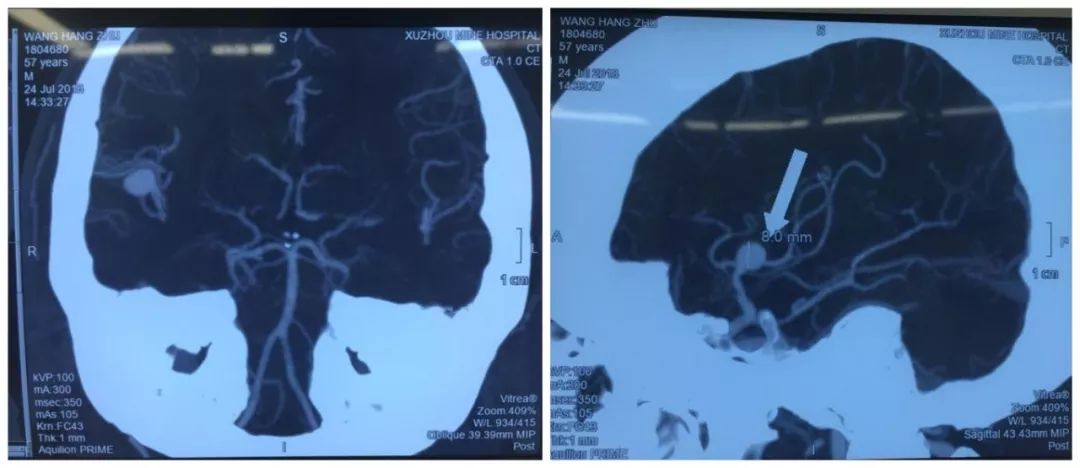

入院后,行頭顱MRI示:右側(cè)大腦中動(dòng)脈分叉部動(dòng)脈瘤;頭顱CTA示:右側(cè)大腦中動(dòng)脈分叉部動(dòng)脈瘤,動(dòng)脈瘤約9.0mm*8.5mm大小,寬頸。礦山醫(yī)院神經(jīng)外科高立志主任告訴王先生的家人,腦動(dòng)脈瘤并非真正的腫瘤,而是由于腦動(dòng)脈內(nèi)腔的局限性異常擴(kuò)大造成動(dòng)脈壁的一種瘤狀突出。由于起病急、癥狀重,被稱為“顱內(nèi)不定時(shí)炸彈”。

對(duì)于動(dòng)脈瘤患者來說,時(shí)間就是生命。經(jīng)家屬同意后,高立志主任決定立即為王先生行開顱動(dòng)脈瘤夾閉術(shù)。手術(shù)持續(xù)了約兩個(gè)小時(shí),非常成功。術(shù)后王先生逐漸康復(fù),生命體征平穩(wěn),無神經(jīng)功能缺失,一周后平安出院。